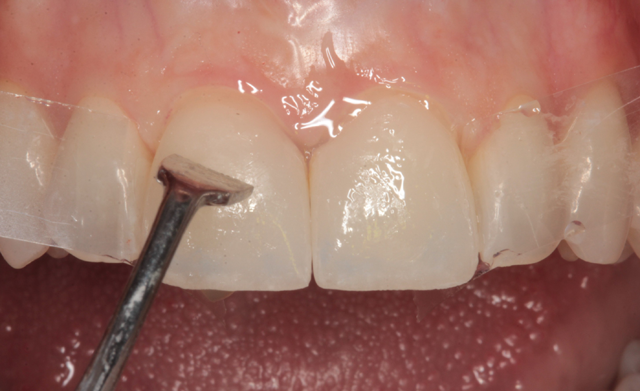

At the delivery appointment, the provisional veneers were removed and the new laminate veneers were tried in using Calibra try in paste (Dentsply/Sirona). The patient was asked to look in a mirror and she approved the new veneers. The veneers were removed and thoroughly cleaned with water spray from an air/water syringe and dried with oil-free air. A silane primer (Calibra Silane Coupling Agent, Dentsply/Sirona) was used to treat the etched intaglio surfaces (Fig. 9), allowed to dwell for twenty seconds and air dried.

Fig. 9 Fig. 10

Celluloid strips were placed distal to both central incisors to protect the adjacent teeth. Phosphoric acid edging gel (Calibra, Dentsply/Sirona) was placed on the prepared enamel surfaces (Fig. 10), thoroughly rinsed after ten seconds (Fig. 11) and air dried (Fig. 12).